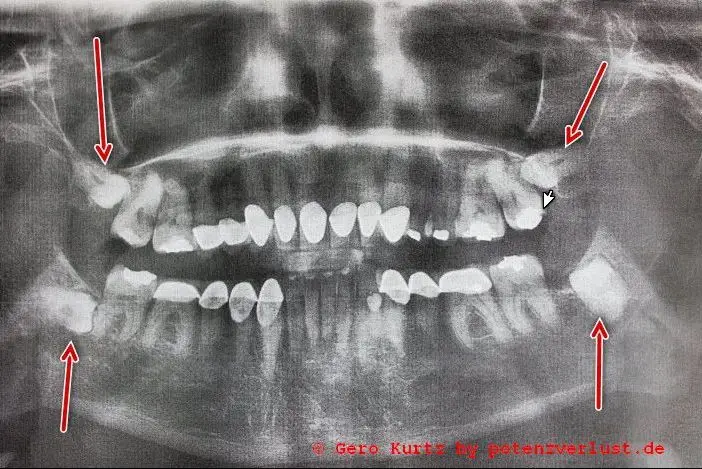

Dort wurde noch einmal das Gebiss mit einem modernen Ganzkieferröntgengerät gescannt. Der Arzt hat sich das dann angeschaut und gemeint, dass die Extraktion unten recht gefährlich sei, da die Zähne sich schon unter den anderen geschoben haben. Ihm ist lieber, wenn dies unter Vollnarkose ausgeführt wird, damit ich mich bei der OP nicht bewege. Eine Lähmung des Gesichtsnervs könnte davon die Folge sein, falls dieser dadurch beschädigt wird. In diesem Falle würde die Vollnarkose auch nichts kosten, da sie medizinisch notwendig sei. Praktischerweise befindet sich eine Anästhesistin im Hause, die in solchen Fällen dann mit dem Team herüberkommt. Die Zahnklinik bildet einen größeren Komplex mit vielen anderen Arztpraxen. In der DDR nannte man so etwas Poliklinik, jetzt wohl eher Ärztehaus.

Röntgenbild Gebiss